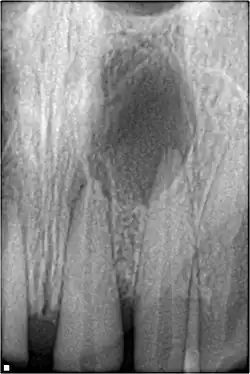

une infection bactérienne de la dent visible sur la radiographie dentaire